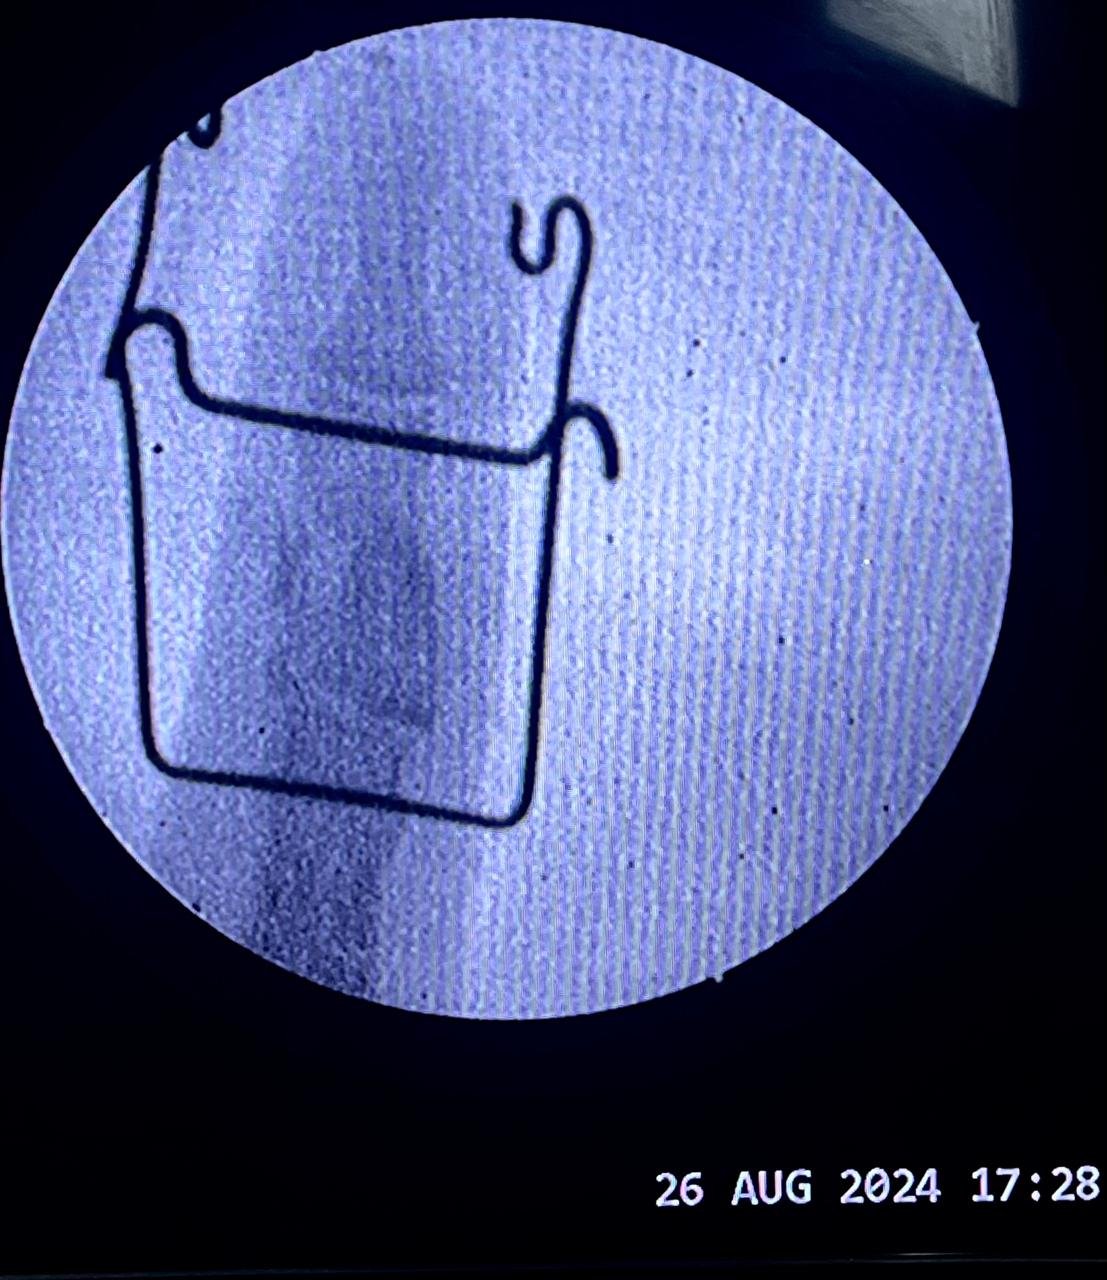

Non union with Broken DCS implant & revision

correction surgery